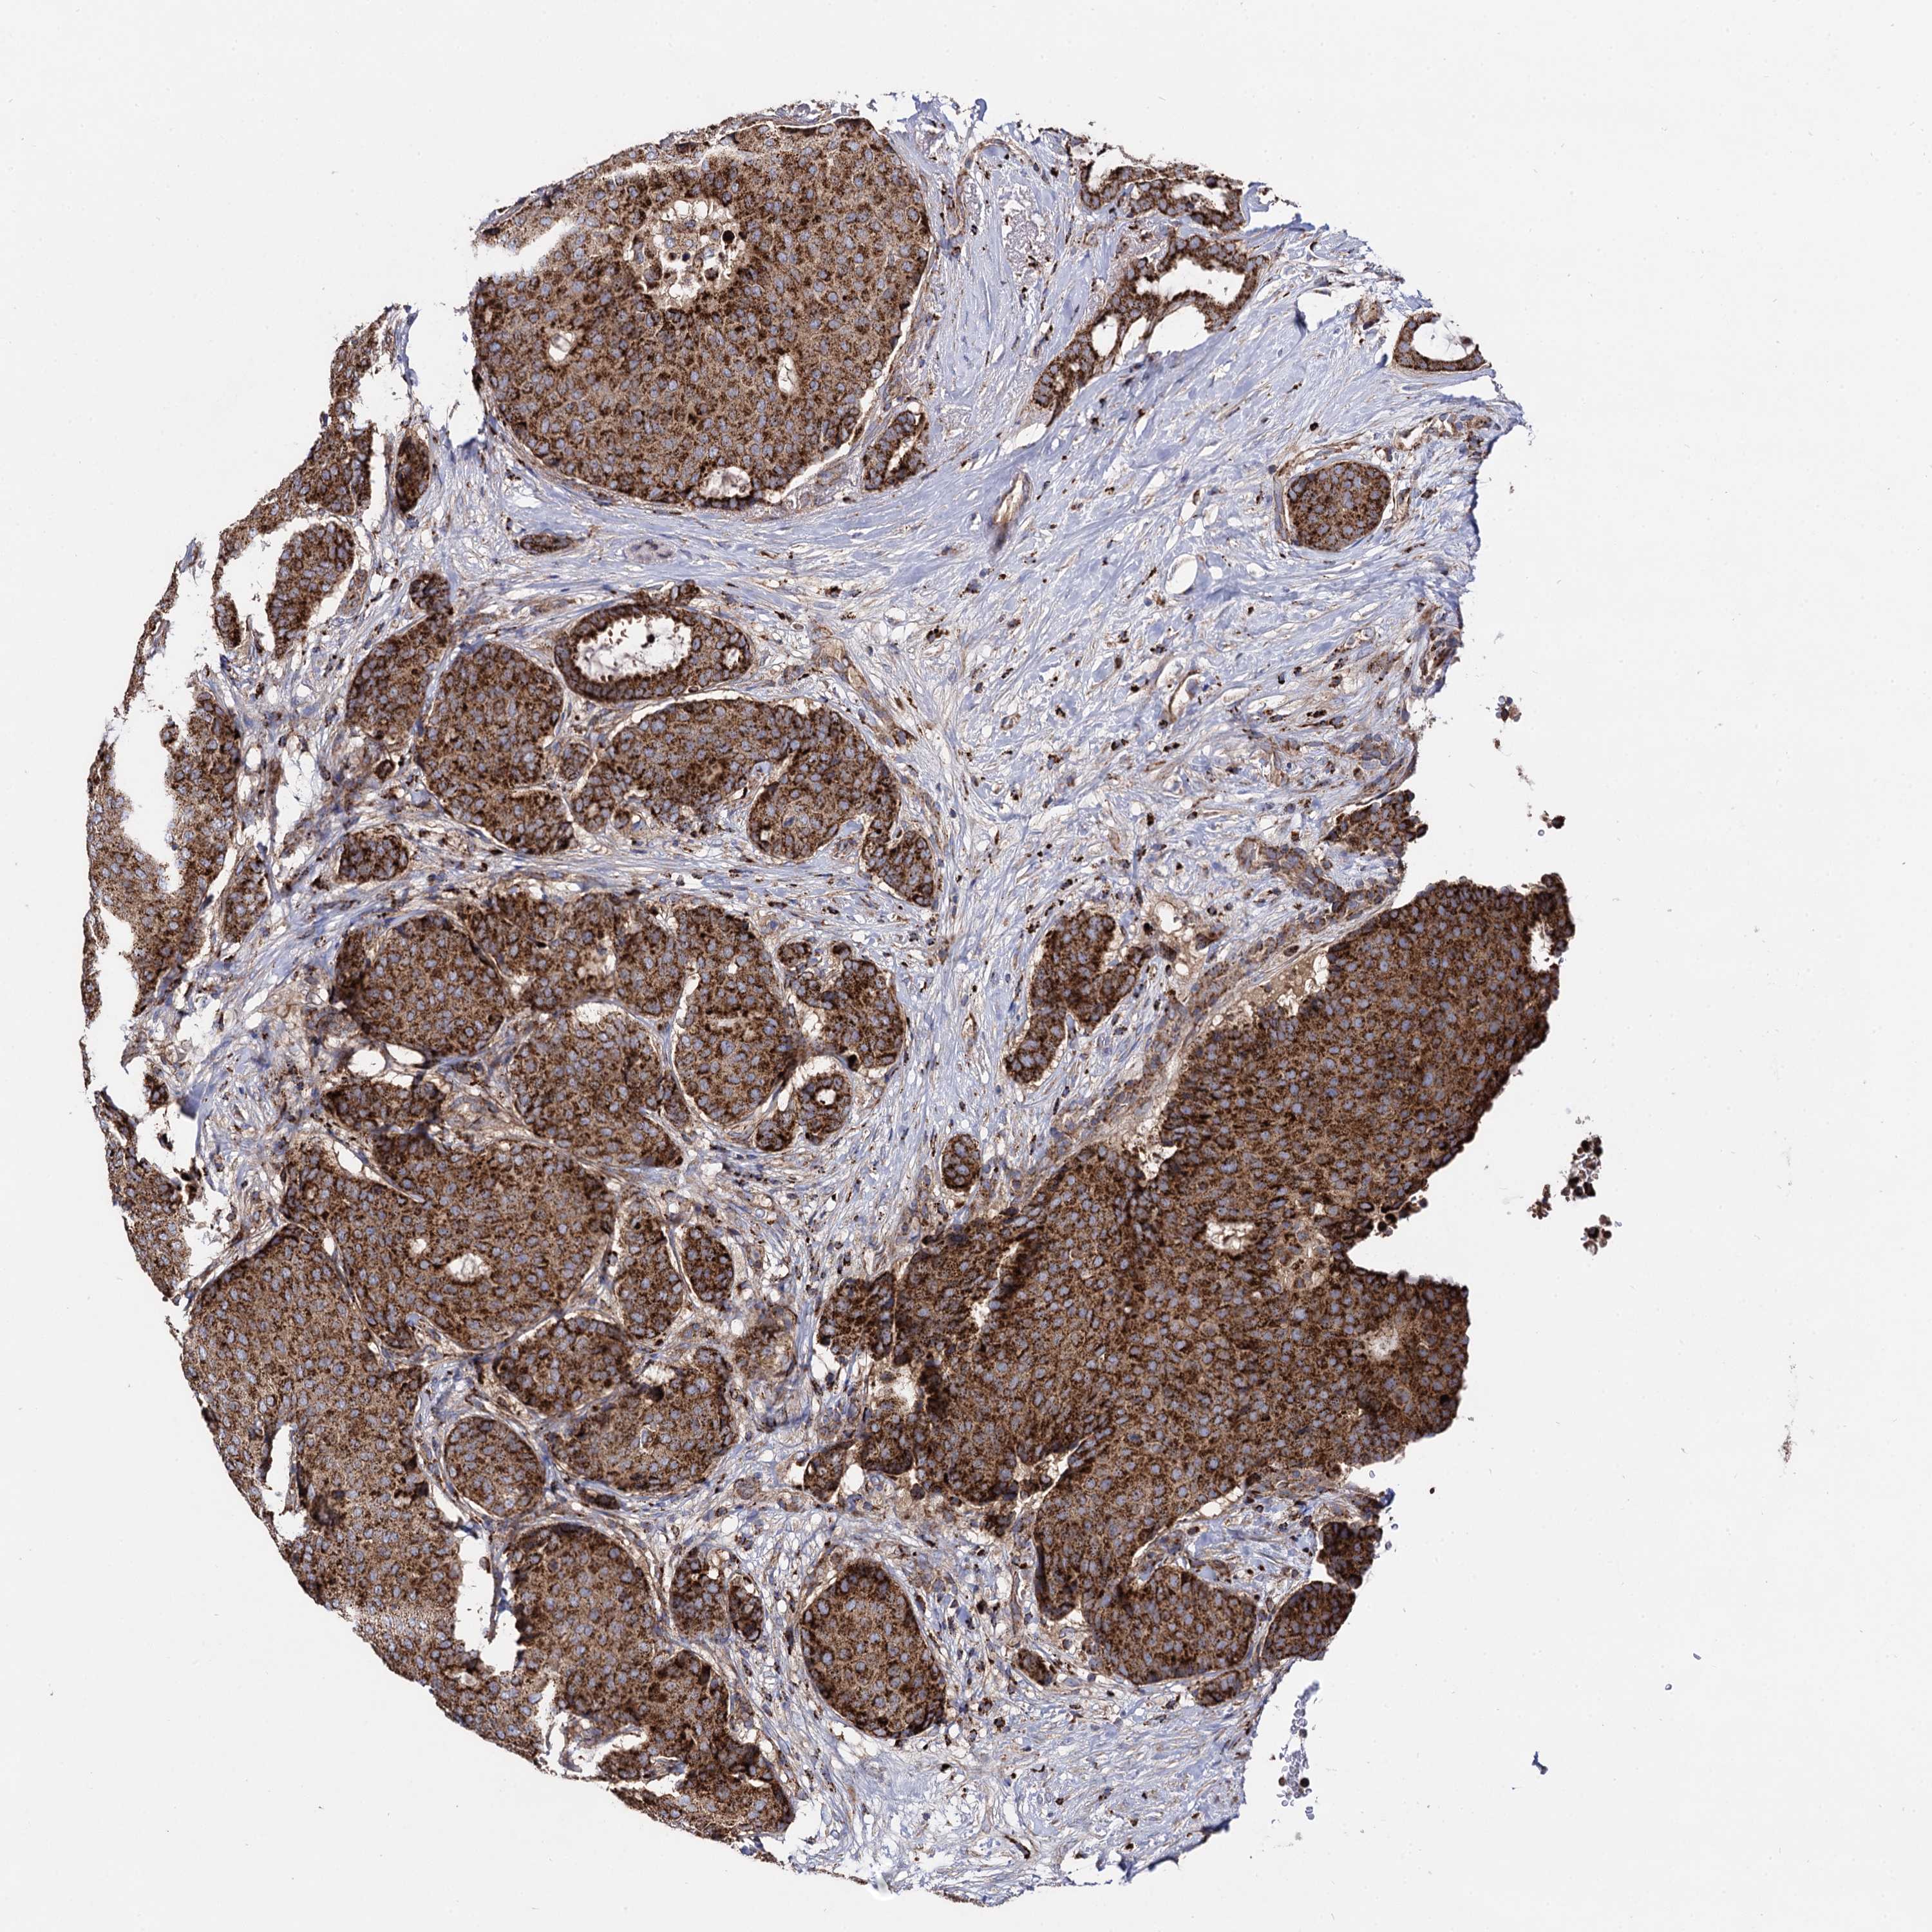

CANCER BREAST CANCER Show tissue menu

BRCA TCGA BRCA VALIDATION PROTEIN EXPRESSION

ANTIBODIES

AND

VALIDATION